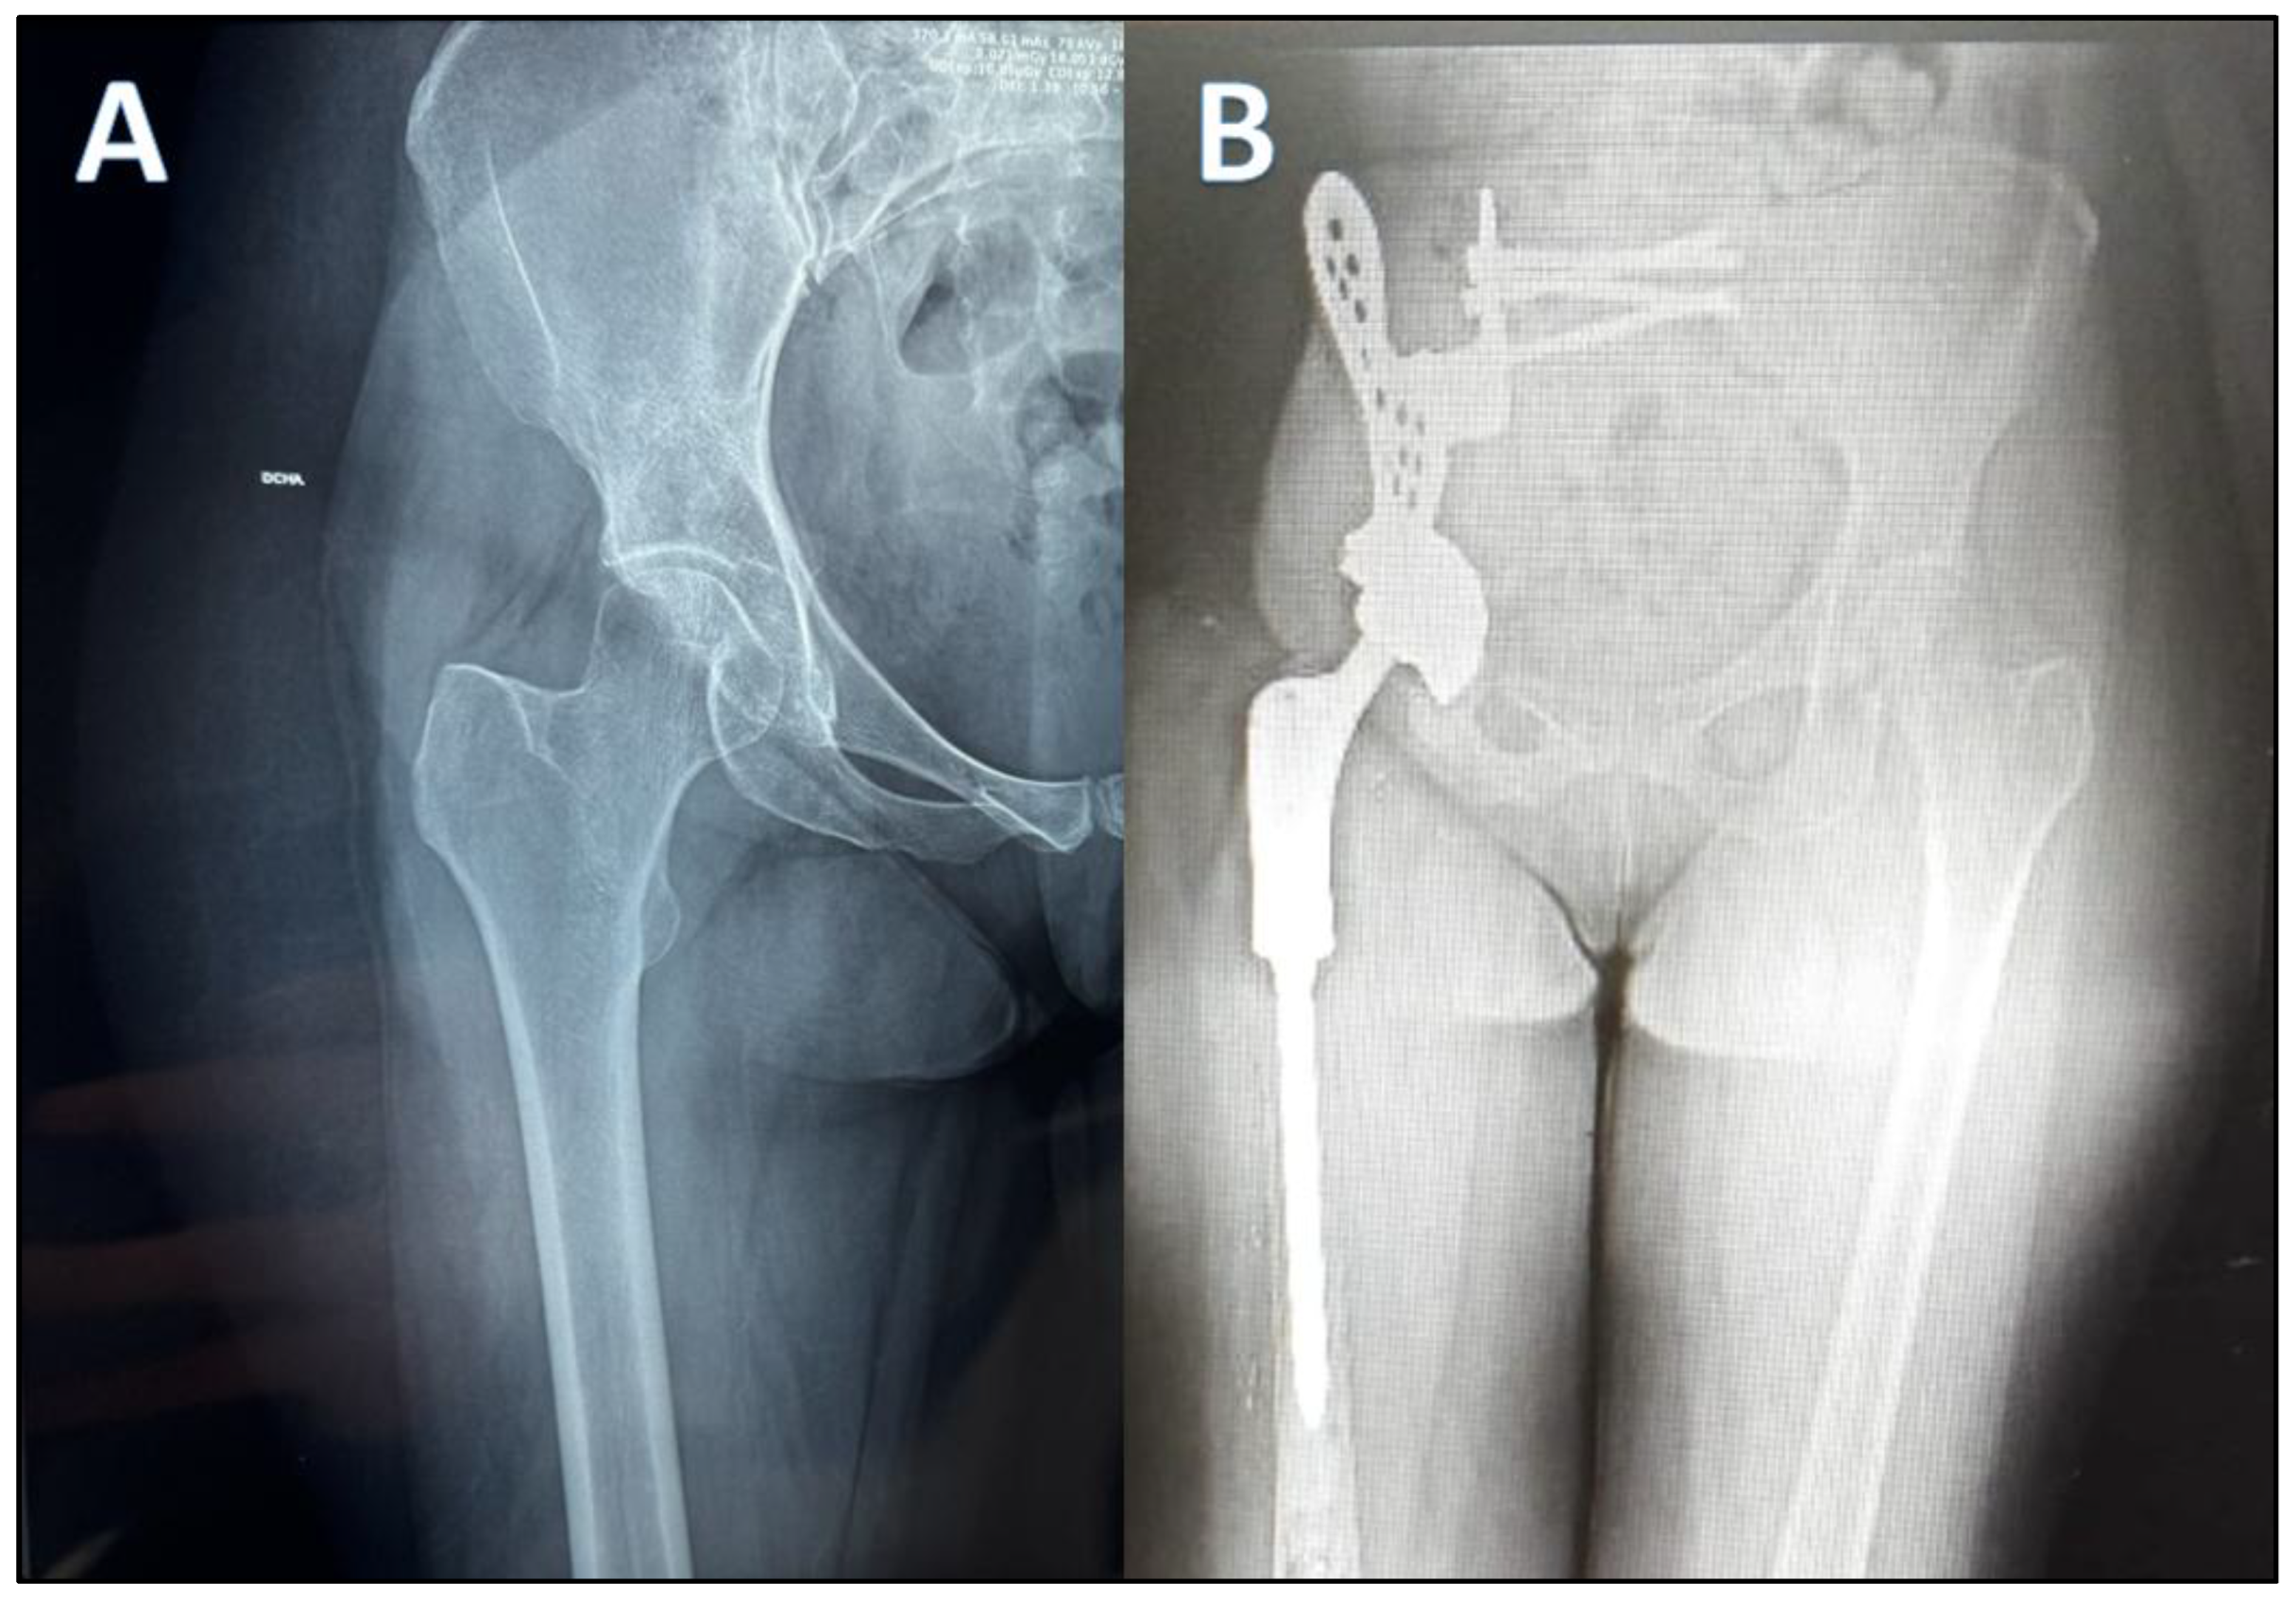

The participant is a 52-year-old woman residing in Granada (Spain), who survived a mesenchymal chondrosarcoma in the right hemipelvis diagnosed in 2015. Faced with an aggressive tumor of the right hemipelvis, of the mesenchymal chondrosarcoma type, the patient underwent surgery in September 2015 at the Ruber International Clinic (Madrid, Spain). Radiographic evaluation revealed an aggressive right iliac tumor with soft tissue extension infiltrating the iliac muscle and hip joint. The surgical intervention involved an internal hemipelvectomy and wide resection of zones 1 and 2 of the right hemipelvis. Extra-articular resection of the right proximal femur was performed in zones 1 and 2 of the right hemipelvis. Reconstruction with a custom-made prosthesis of the right hemipelvis (INPOL) and proximal femur (DePuy) was carried out. The hemipelvis prosthesis was osteosynthesized to the sacrum using cannulated screws and to the proximal femur with a double-mobility cup. Reconstruction of soft tissues used a Vertical Rectus Abdominis Myocutaneous (VRAM) flap (Figure 1).

Figure 1. Aggressive tumor of apparent origin in the right acetabular region with poorly defined and permeable borders that gives rise to a large, solid, and heterogeneous soft tissue mass that infiltrates the right iliopsoas muscle. It presents intra-articular extension occupying the upper and anterior part of the joint, with reactive edema (A). Internal hemipelvectomy including right hemipelvis plus femoral joint and resection of the right proximal femur (B).